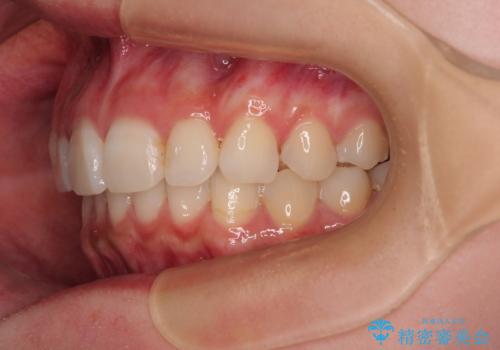

- 前歯のデコボコと突出感を気にして来院された患者様です。

極力目立たない装置を希望とのことで、インビザラインを用いて非抜歯で矯正治療を行うこととしました。

事前に親知らず2本を抜歯し、多少歯列を後方に移動できるように準備をした上で、なるべく歯と歯の間を削ることなくデコボコを解消できるように計画しました。

前歯の捻れを改善するとともに、口元が少しでも引っ込むように治療計画を立て、仕上げることができました。

長時間の装着を徹底し、遠方からの通院にもかかわらずしっかりと通院いただき、予想よりも早く治療を終えることができました。